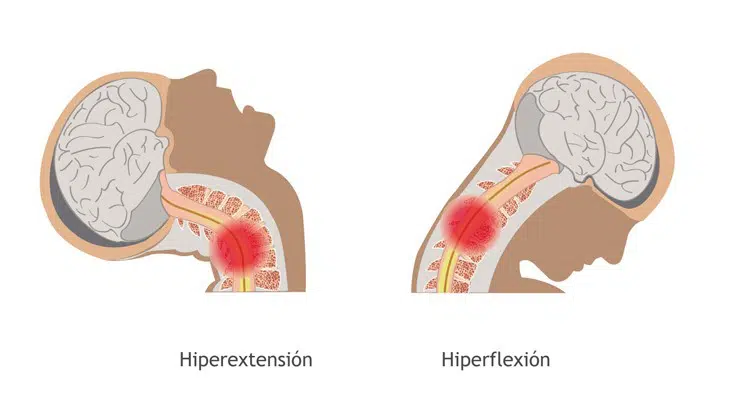

Consecuencias a medio-largo plazo de un latigazo cervical

¿Conoces las secuelas del latigazo cervical? El síndrome del latigazo cervical representa en la actualidad, según datos de la Dirección General de Tráfico, un 34% de las lesiones causadas por un accidente en carretera. Es decir, aproximadamente 1 de cada 3 víctimas presenta esta dolencia. En Barcelona Quiropractic es muy frecuente ver a personas que […]

¿Qué es y cómo tratar un latigazo cervical?

Cada vez es mayor la preocupación por las causas y consecuencias de lo que hoy en día se podría incluir en ese grupo de las “enfermedades de la civilización”: el latigazo cervical. Y es que estas lesiones y en particular el desarrollo del dolor crónico y la incapacidad, son un problema clínico y social en […]